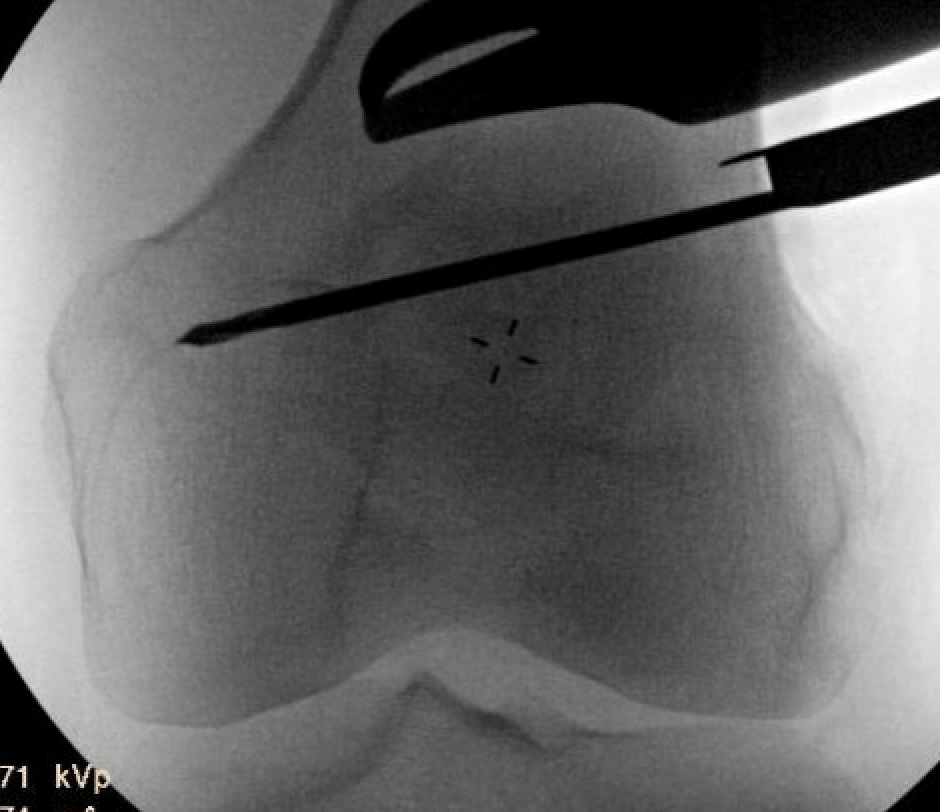

Osteotomy

- insert guide wires

- proximal lateral to distal medial

- proximal 1 - 2 cm above flare of lateral condyle

- aim towards adductor tubercle

- risk of medial hinge fracture reduced if osteotomy at or distal to adductor tubercle

- ensure these are perpendicular to the femoral shaft in the sagittal plane

- above patellofemoral joint and posterior condyles

- stop osteotomy 1 cm short of medial cortex